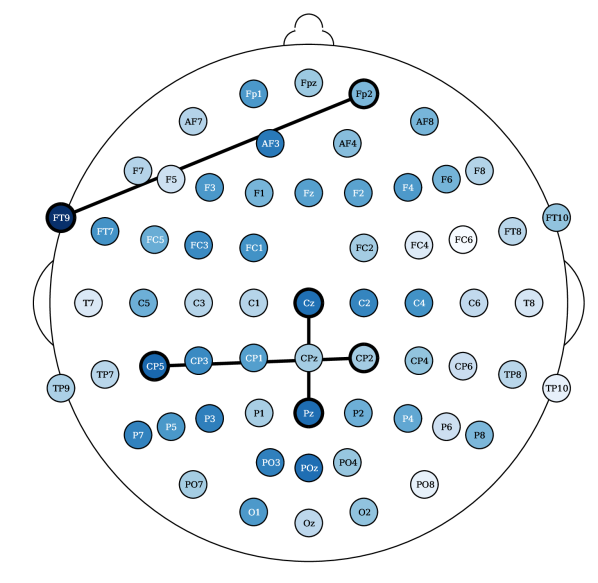

Most relevant electrode relations. Consider the relevance of the attention scores, computed from models (ii) and (iv), both having topographical attention at the EEG channel dimension, and model (iv) with projected random Fourier features in the latent space. These relevances were propagated, using the LRP algorithm [36] described in Appendix 0.E, through the attention style based posterior. Figure 5 shows the relevances plotted in a white to blue scale, from less relevant to most relevant, respectively. The latter only shows the edges that are above the percentile. The presence of an edge between electrodes suggests that either this connection yields a Markovian property for the EEG instance or, otherwise, it is relevant to add fMRI style conditioned on these connections (recall from Section 3.2 that posterior conditions the latent EEG representation such that ). For resting state fMRI, both Figures 10(a) and 5(a) show connections of parietal and occipital channels (O2 electrode in Figure 10(a) and Pz electrode in Figure 5(a)) with frontal and central channels to be the most relevant (above the 99.7 percentile of relevance). Figure 10(a) reports an additional connection between the Oz and PO9 electrodes, a correspondence between an occipital and a parietal-occipital electrode, which is in accordance with connectivity observations reported by Rojas et al. [6]. There were no reported relevances for the electrodes (T) placed in the temporal regions for resting state settings. In contrast, in task-based fMRI synthesis, relevant relationships between temporal (FT9 and TP9) and frontal/central (Fp2 and C1/C2, respectively) electrodes were reported, see Figures 10(b) and 5(b). In both of these figures, connections between central and parietal electrodes were observed. Particularly, there were reported connections between Cz with Pz and CP5 and CP2 electrodes in Figure 10(b). And connections between Pz and P8 with CPz electrodes in Figure 5(b).

Laboratory setup impacts EEG to fMRI synthesis. The results show that it is more difficult, according to the RMSE metric, to synthesize task-based fMRI than resting state. This observation is in contrast with studies that report that resting state fMRI is inherently more complex than task based fMRI [37]. The SSIM metric, in contrast to the RMSE, shows less significant differences for the Oddball recordings in favor of fMRI synthesis in the resting state. However, the CN-EPFL dataset is not in accordance with the latter. This performance heterogeneity across the datasets may not only rise from the characteristics of the recording sessions, but may also be also propelled by the different preprocessing techniques employed. Each dataset is publicly available and is supported with published studies, having unique equipment, experimental protocols, and algorithms. CN-EPFL dataset is the most complete one, with a total of 20 individuals and with a resolution of mm, which makes a total of voxels. These differences, caused by working with 3 Tesla (CN-EPFL dataset) versus 1.5 Tesla (NODDI and Oddball datasets) scanners, significantly impact the spatial resolution, which for the datasets NODDI and Oddball produce and voxels, respectively, with around mm voxel size. One has to further account for the original recording artifacts and disruptions caused by the applied preprocessing techniques. For instance, Oddball dataset contains intra and inter individual wise misalignments across fMRI volumes. This may be the cause of poorer performance of all methods when compared to the other datasets. In addition, Oddball relies on a different EEG electrode positioning system, having a total of electodes that were not placed in accordance with the 10-20 system [26]. Although NODDI and CN-EPFL recordings are in accordance with this system, each selected unique electrode locations (see the different electrode placements between Figures 5(a) and 5(b)). Finally, the different EEG sampling frequencies, with Hz, Hz and Hz considered in NODDI, Oddball and CN-EPFL recordings, respectively, further affect architectural operations and subsequently impact the learning.